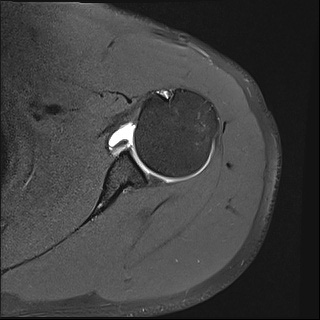

관절내시경을 통해 파열된 구조물을 봉합하여 복원하는 수술이 시행됩니다.

관절와순의 아랫부분 인방 카르트 파열로 이를 봉합해준 모습

수술 전

수술 후